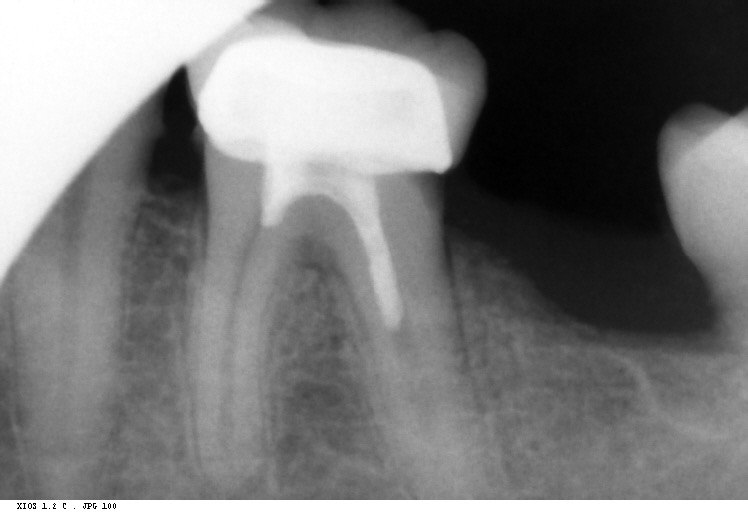

Question 1: What materials cannot be seen in the print of the X ray?